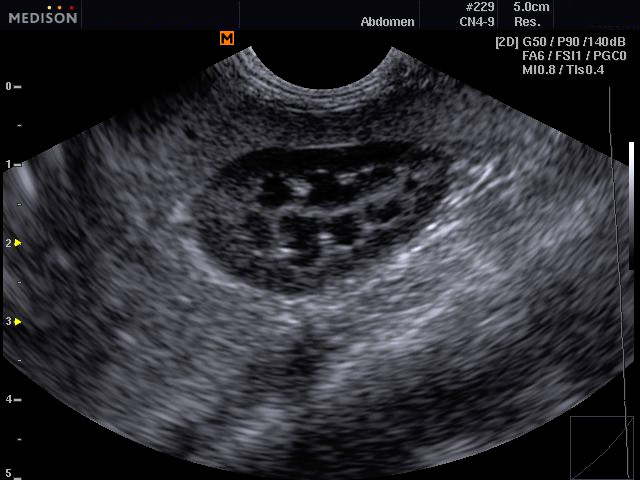

SonoVet ultrahang esetkép microconvex vizsgálófejjel